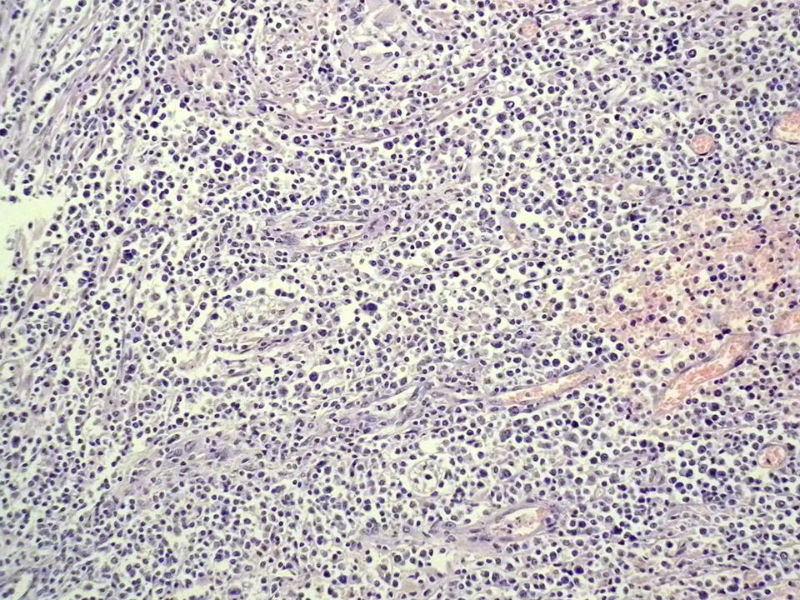

女,53岁,横结肠有9X6厘米大小溃疡,手术切除。

中老年人,溃疡很大,可见淋巴浆细胞样细胞弥漫浸润,散在大细胞,疑非霍奇颈淋巴瘤,倾向MALT伴浆样分化,不知是否破坏肌层?可否传肌层图?需IHC标记,鉴别淋巴瘤、腺癌及其它。

肉眼观仅是溃疡?有没有肠壁增厚、隆起?周围粘膜情况?肌层情况?有淋巴浆细胞样细胞、中心细胞,散在少量不成片的大细胞,不排除MALToma伴大细胞转化。

本例肉眼溃疡如溃疡性结肠炎,肠壁无明显增厚,表面辅以坏死,溃疡边缘稍隆起。镜下淋巴样细胞局限在粘膜层,肌层未见。谢谢!